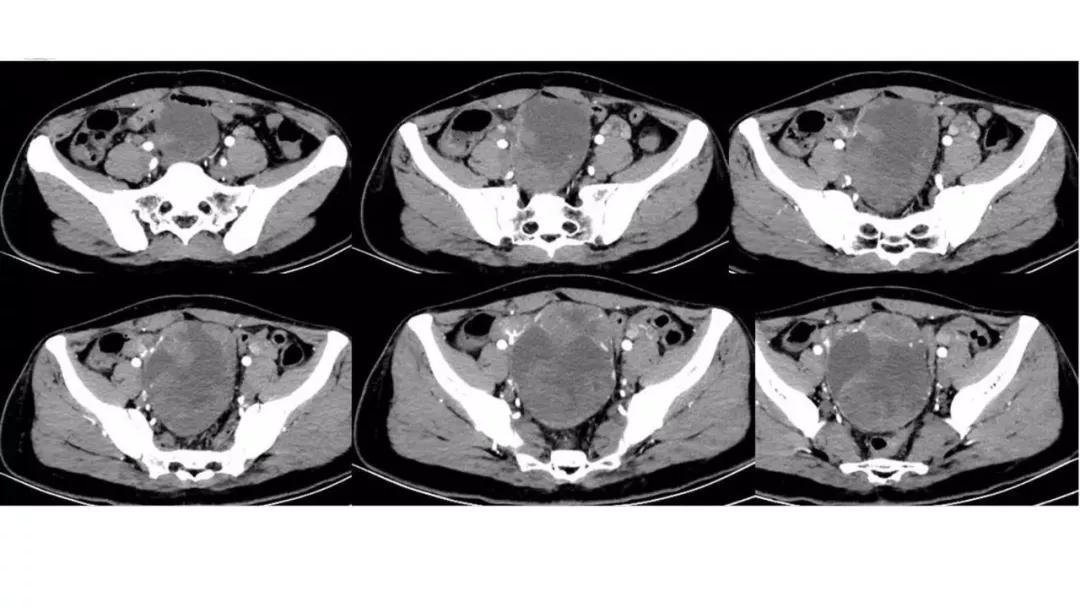

病例4 女,32岁,以“月经量增多伴经期延长半年。”

缘于患者入院前半年无明显诱因出现月经量增多,卫生巾由原来3包余增至5包不等,伴血块,经期由原来7天延长至10-15天不等,无痛经,无月经周期改变,无阴道异常排液,无畏冷、发热,无头晕、乏力等不适,未重视,未诊治。期间症状持续。2月前就诊我院,查彩超示:“子宫体大小约5.7*5.3*4.6cm,内膜厚约0.6cm,回声不均,左卵巢旁探及大小约4.2*3.5cm低回声区。”建议治疗,患者及家属表示考虑。期间症状持续,今就诊我科门诊,要求住院手术治疗,无腹痛等不适,门诊拟“卵巢囊肿”收住入院。既往史:2007年剖宫产一次,术顺。月经史:15 7/25 lmp2018.05.14,量中,无痛经。婚育史:已婚,1-0-3-1,末孕2007年剖宫产娩一男婴,儿子及丈夫体健。个人史、家族史均无特殊。

CA125 335.5(U/mL);2018-05-30 彩超:子宫宫体大小约5.6㎝×6.3㎝×4.9㎝,形态正常,宫壁回声欠均,内膜厚约1.8cm,回声不均。CDFI:子宫内未见明显异常彩色血流信号。左附件区探及一混合回声团块,大小约9.8㎝×7.9㎝,CDFI:其实性部分可见少许彩色血流信号。右附件区未见明显包块回声。

病理:卵巢子宫内膜样癌